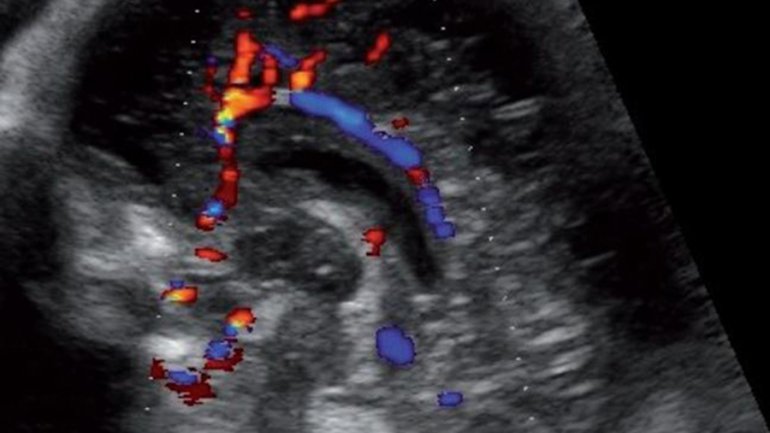

Ultraschall 16. SSW

Auf dem Ultraschallbild ist die Nabelschnur zu sehen; sie versorgt das Baby mit Nährstoffen und Sauerstoff und transportiert Abfallstoffe ab. Der Blutfluss in den drei Blutgefäßen (1 Vene, 2 Arterien) lässt sich mithilfe des sogenannten Dopplerultraschalls farbig darstellen und untersuchen.